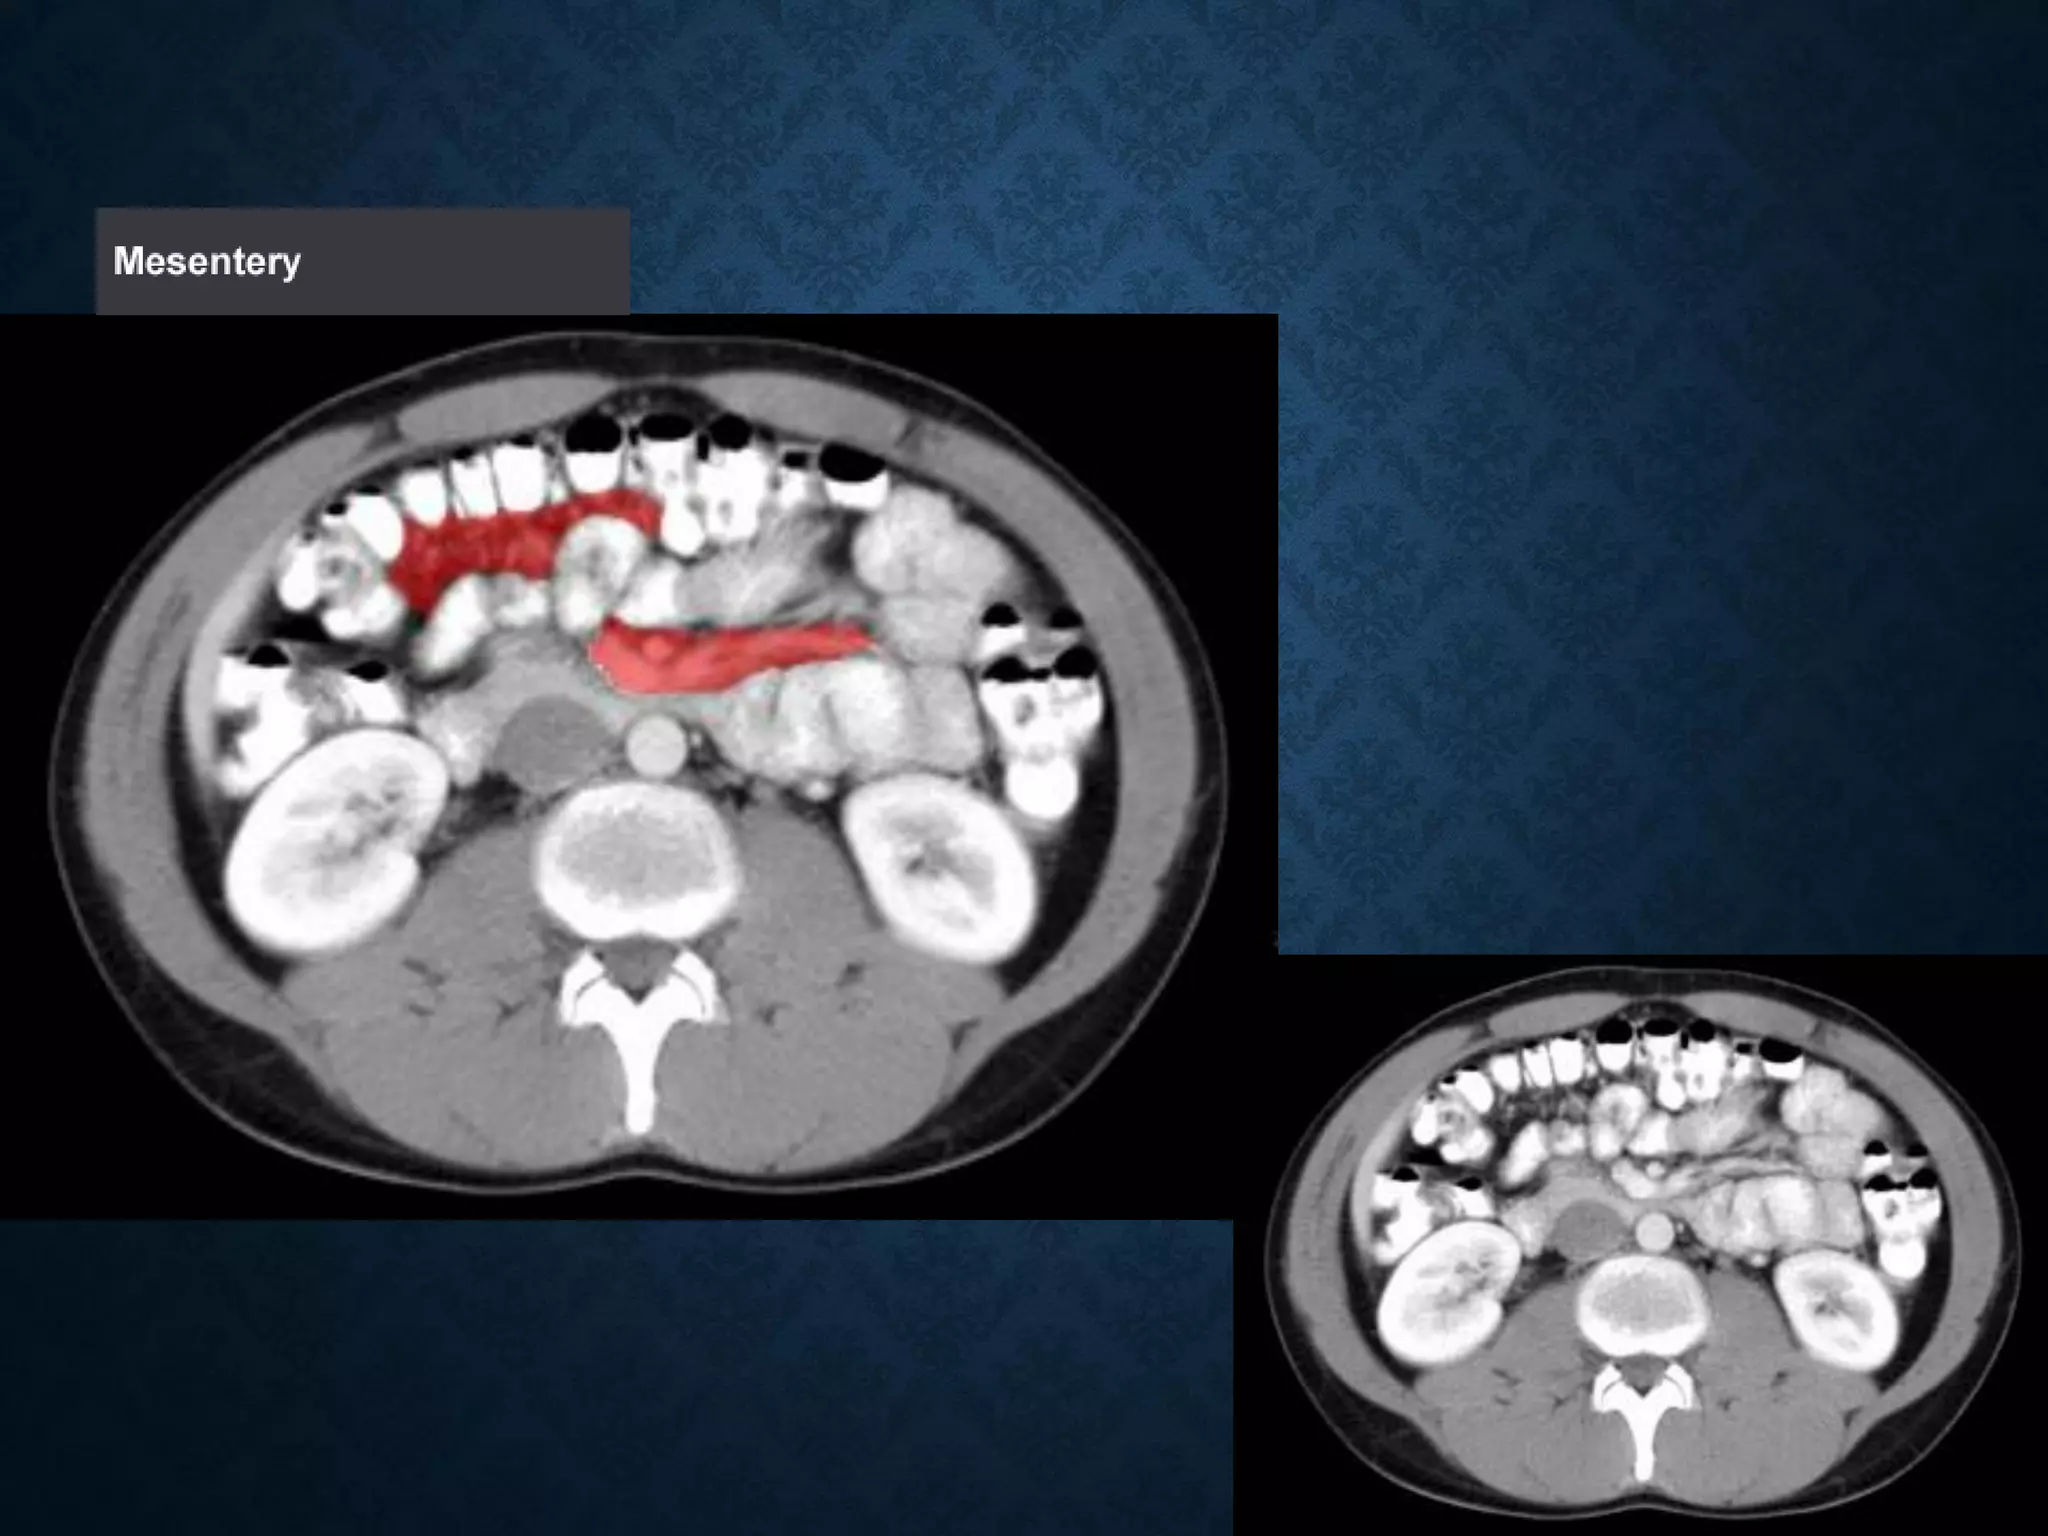

Identify the following structures in the body CT to the right. To view the location of the structure in the image click on

the label at the left and the structure will be indicated in the image. Abdominal CT scans typically begin just above

the diaphragm, so the first slice you see is of the lower chest.